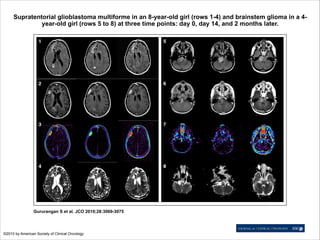

Supratentorial glioblastoma multiforme in an 8-year-old girl (rows 1-4) and brainstem glioma in a 4year-old girl (rows 5 to 8) at three time points: day 0, day 14, and 2 months later.

Gururangan S et al. JCO 2010;28:3069-3075

©2010 by American Society of Clinical Oncology

Supratentorial glioblastoma multiformein an 8-year-old girl (rows 1-4) and brainstem glioma in a 4year-old girl (rows 5 to 8) at three time points: day 0, day 14, and 2 months later. Gururangan S et al. JCO 2010;28:3069-3075 ©2010 by American Society of Clinical Oncology